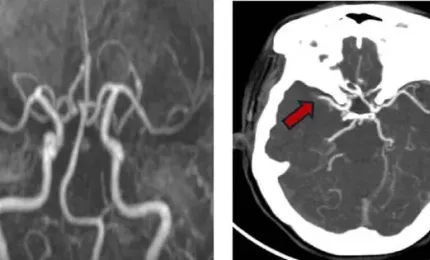

Người phụ nữ liên tiếp bị 2 cơn đột quỵ

TPO - Tưởng như đã vượt qua cơn nguy hiểm sau lần đột quỵ đầu tiên, người phụ nữ 57 tuổi không ngờ lại đối mặt tiếp c